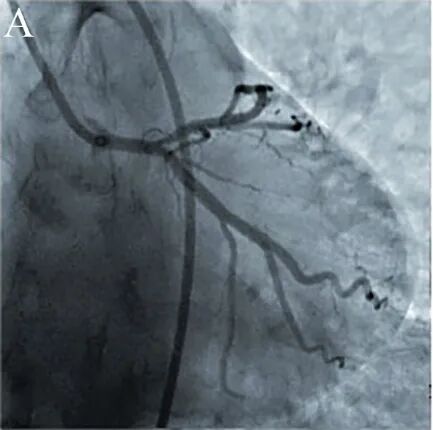

图5 冠脉造影[4]。

53岁男性劳力性心绞痛,造影显示前降支开口孤立性狭窄70%。